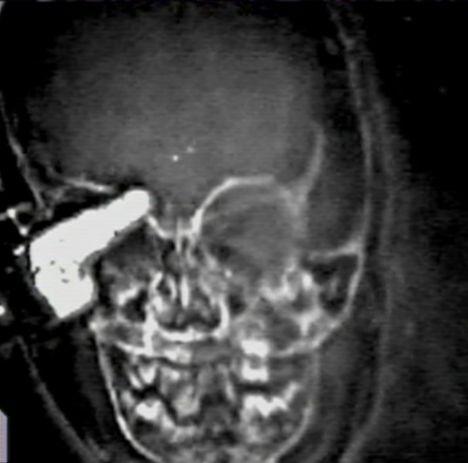

Ребенок остался невредимым после того, как связка металлических ключей пробила его голову

В сентябре 2008 года Николасу Холдермэну (Nicholas Holderman) было только 17 месяцев, когда он упал в своем доме и приземлился на связку ключей. Один из ключей проколол его веко, проткнул глаз и пробился в его мозг.

Рентген показал, что один из ключей проник ребенку в мозг.

Медикам удалось хирургическим путем извлечь ключ, не причинив при этом никакого вреда мозгу Николаса. Как сообщается, еще через четверть часа они установили, что и зрение мальчика не пострадало после несчастного случая.